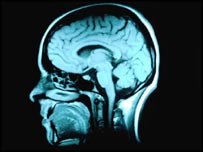

دانشمندان با تصویر برداری از مغز به سرنخی برای پی بردن به چگونگی خلق تصویر ذهنی که ما از آینده خود می سازیم، دست یافتند. پژوهشگران دانشگاه واشنگتن می گویند یک نقطه خاص از مغز در هنگام فکر کردن در باره آینده فعال می شود. چنانچه این تحقیق به مراحل پیشرفته تری برسد می تواند به متخصصان برای درک آسیب های ناشی از ضربه، جراحت و بیماریها در این منطقه از مغز یاری رساند. این یافته ها با آسیب های مشخص شده در مغز بیمارانی که قابلیت تفکر در باره آینده را از دست داده اند، مطابقت می کند. مغز همچنان تنها عضوی از بدن باقی مانده است که ناشناخته مانده است، اما استفاده ازتصویر برداری ام ار آی برای توضیح سازو کارآن در سالهای اخیر رواج یافته است. هنگامی که بیماران یا داوطلبان تحت تصویربرداری ام ار آی قرار می گیرند و از آنها درخواست می شود که فکر کنند یا بطرز خاصی تحرک داشته باشند، نقاط مشخصی از مغز در تصویر اسکن"روشن می شوند" که نشانگر افزایش فعالیت الکتریکی در این مناطق است. این شیوه تا بدانجا تکمیل شده است که دانشمندان با نگاه کردن به نقاط فعال شده در مغز، تقریبا می توانند بفهمند که بیماران درباره چه چیزی فکر می کنند. تازه ترین پروژه در این زمینه بر تفکر منطقی که منحصر به انسان است، متمرکز شده است، قابلیت خلق تصور ذهنی از رخدادهای که هنوز به وقوع نپیوسته اند. پژوهشگران 21 داوطلب را مورد ام آر ای قرار دادند و نتایج اسکن مغز آنها را در زمانی که از آنها خواسته شده بود به طور محض رخدادهای مربوط به آینده را در ذهن خود مجسم کنند و زمانی که گذشته را به خاطر می آوردند، را با یکدیگر مقایسه کردند. فعال شدن مغز نتایج این مقایسه به وضوح نشانگر تفاوت بین تفکر درباره جشن تولدی که سپری شده بود و جشن تولدی که در آینده رخ خواهد داد، بود. بطور خاص، وقتی به آینده فکر می کنیم، سه بخش خاص از مغز فعال می شوند: کرتکس جانبی چپ ، پریسنوس چپ و بخش راست عقب مخچه. این بخش های مغز در حال حاضر به عنوان بخش هایی که در هنگام تصور ذهنی از تحرک بدنی فعال می شوند، شناخته می شوند، بدین معنا که وقتی مغز درباره آینده فکر می کند، فعالیت ها و تحرکاتی در این بخش ها رخ می دهد. نمونه دیگری از این مورد مربوط به تحقیق دیگری است که نشانگر فعال شدن بخش های مشابه ای از مغز درزمان حرکت دادن بازو و وقتی بود که از داوطلبان خواسته شد تا درباره بازی کردن بیس بال فکر کنند. نتایج این آزمایش ها با سایر مطالعات مربوط به بیمارانی که از آسیب مغزی در همین مناطق رنج می برند و دیگر قادر به تفکر در باره رخدادهای آتی نیستند، همخوانی دارد. پژوهشگران درباره این مطالعه نوشته اند: "شاید یکی از مهم ترین توانایی های سازگاری ذهن بشر، قابلیت رفتار اصولی در پیش بینی پیامدهای آتی باشد. بخش مهمی از تفکرات روزانه ما وابسته به قابلیت تصور کردن وضعیت خودمان در رخدادهای آتی است." بهر روی، این پژوهشگران بطرز آشکاری تاکید کرده اند که تحقیقات آتی برای درک دقیق تر سازوکار مغز در هنگام تفکر در باره آینده ، ضروری است. |